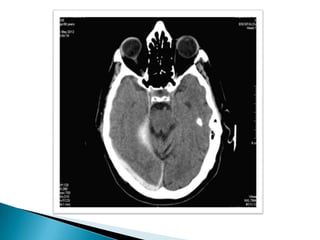

Paciente masculino de33 años de edad que ingresa en el día 13-07-12 guardia del Nombre: Marcelo Blaszczyszyn presentando traumatismo craneoencefálico provocado por caída de un tercer piso. Al momento del examen presenta Glasgow3- 15 HTO 18,9 % HB 6 Plaquetas 66

TC cerebro: Presencia de trazo fracturario a nivel occipital, temporo-parietal izquierda y hundimiento de región derecha.  Imagen hiperdensa en región fronto- temporo-parietal izquierda, con desplazamiento de la línea media y borramiento de ventrículos laterales compatible con hemorragia subdural.  Hiperdensidad compatible con hemorragia subaracnoidea.  Cefalohematoma que recorre toda la zona occipital y temporal